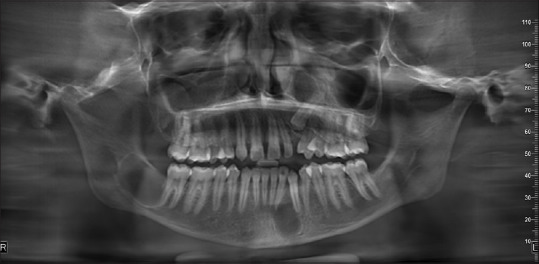

Rationale: The importance of a comprehensive and interdisciplinary approach in early diagnosis and managing patients with rare genetic disorders must be highlighted appropriately. This case report delves into the complex clinical presentation of a patient with Gorlin-Goltz Syndrome, emphasizing the multifaceted challenges encountered during diagnosis, treatment, and long-term management and involves a detailed exploration of the patient's clinical history, encompassing cutaneous manifestations, skeletal anomalies, and neurological findings radiological imaging also plays a pivotal role in guiding towards the diagnostic process and forming the basis for a multidisciplinary approach for management of the patient.

Patient concerns: A previously treated case for pain in lower left tooth region, patient concerns for pain and pus discharge from same region.

Diagnosis: After thorough clinical and radiographic findings patient was diagnosed with Gorlin goltz syndrome having multiple cysts.